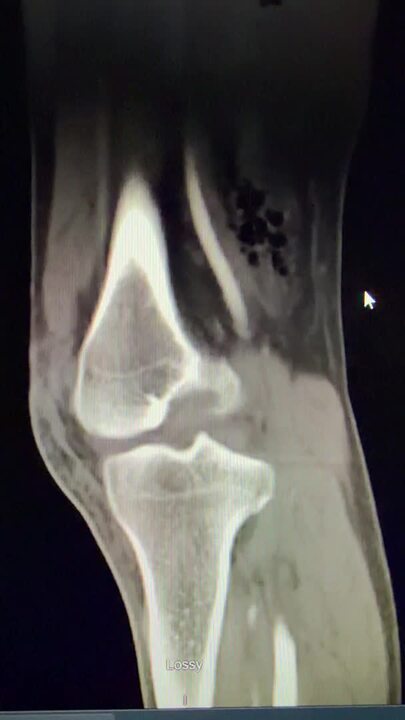

Video of patient in cohort 1 with no knee joint violation